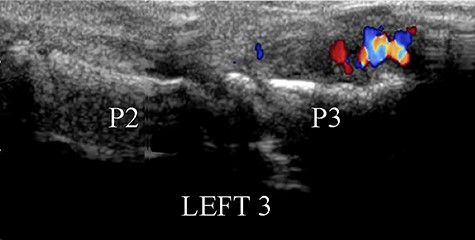

Conventional radiography showed a discrete deformation and irregular density of the phalangeal tuft (Fig. 2). The color Doppler ultrasound showed a hypervascularized pattern of swollen soft tissues on the dorsal aspect of the phalangeal tuft, suggesting a glomus tumor (Fig. 3). A CT scan showed a small lucent bone area within a focal hypertrophy of the phalangeal tuft with adjacent bone sclerosis (Fig. 4). Based on this latest examination, the diagnosis of OO of the distal phalanx was proposed as diagnosis.

Dorsal view of color Doppler ultrasound showing the hypertrophy of the soft tissues near the phalangeal tuft, with a pattern of hypervascularization.